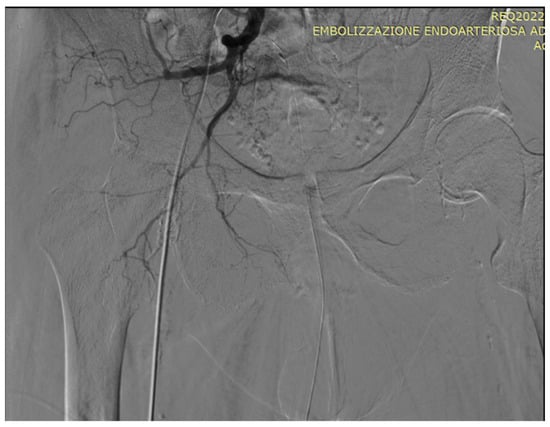

5. A Suggested Algorithm and a Demonstrative Case Report

Technical Details of PAE